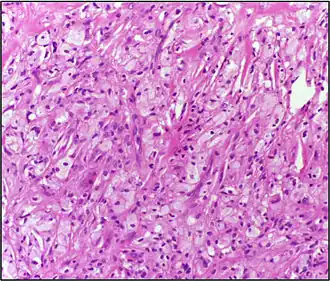

Histologie d'un xanthome, montrant des cellules avec de larges plages d'inclusions lipidiques, grossissement x 10, hématoxyline et éosine. Kumar et al. Cases Journal 2008

Histologie (Microscopie)

• Infiltrat dermique d'histiocytes géants parfois polynucléés (cellules de Touton) dont le cytoplasme spumeux est chargé de lipides : cholestérol essentiellement